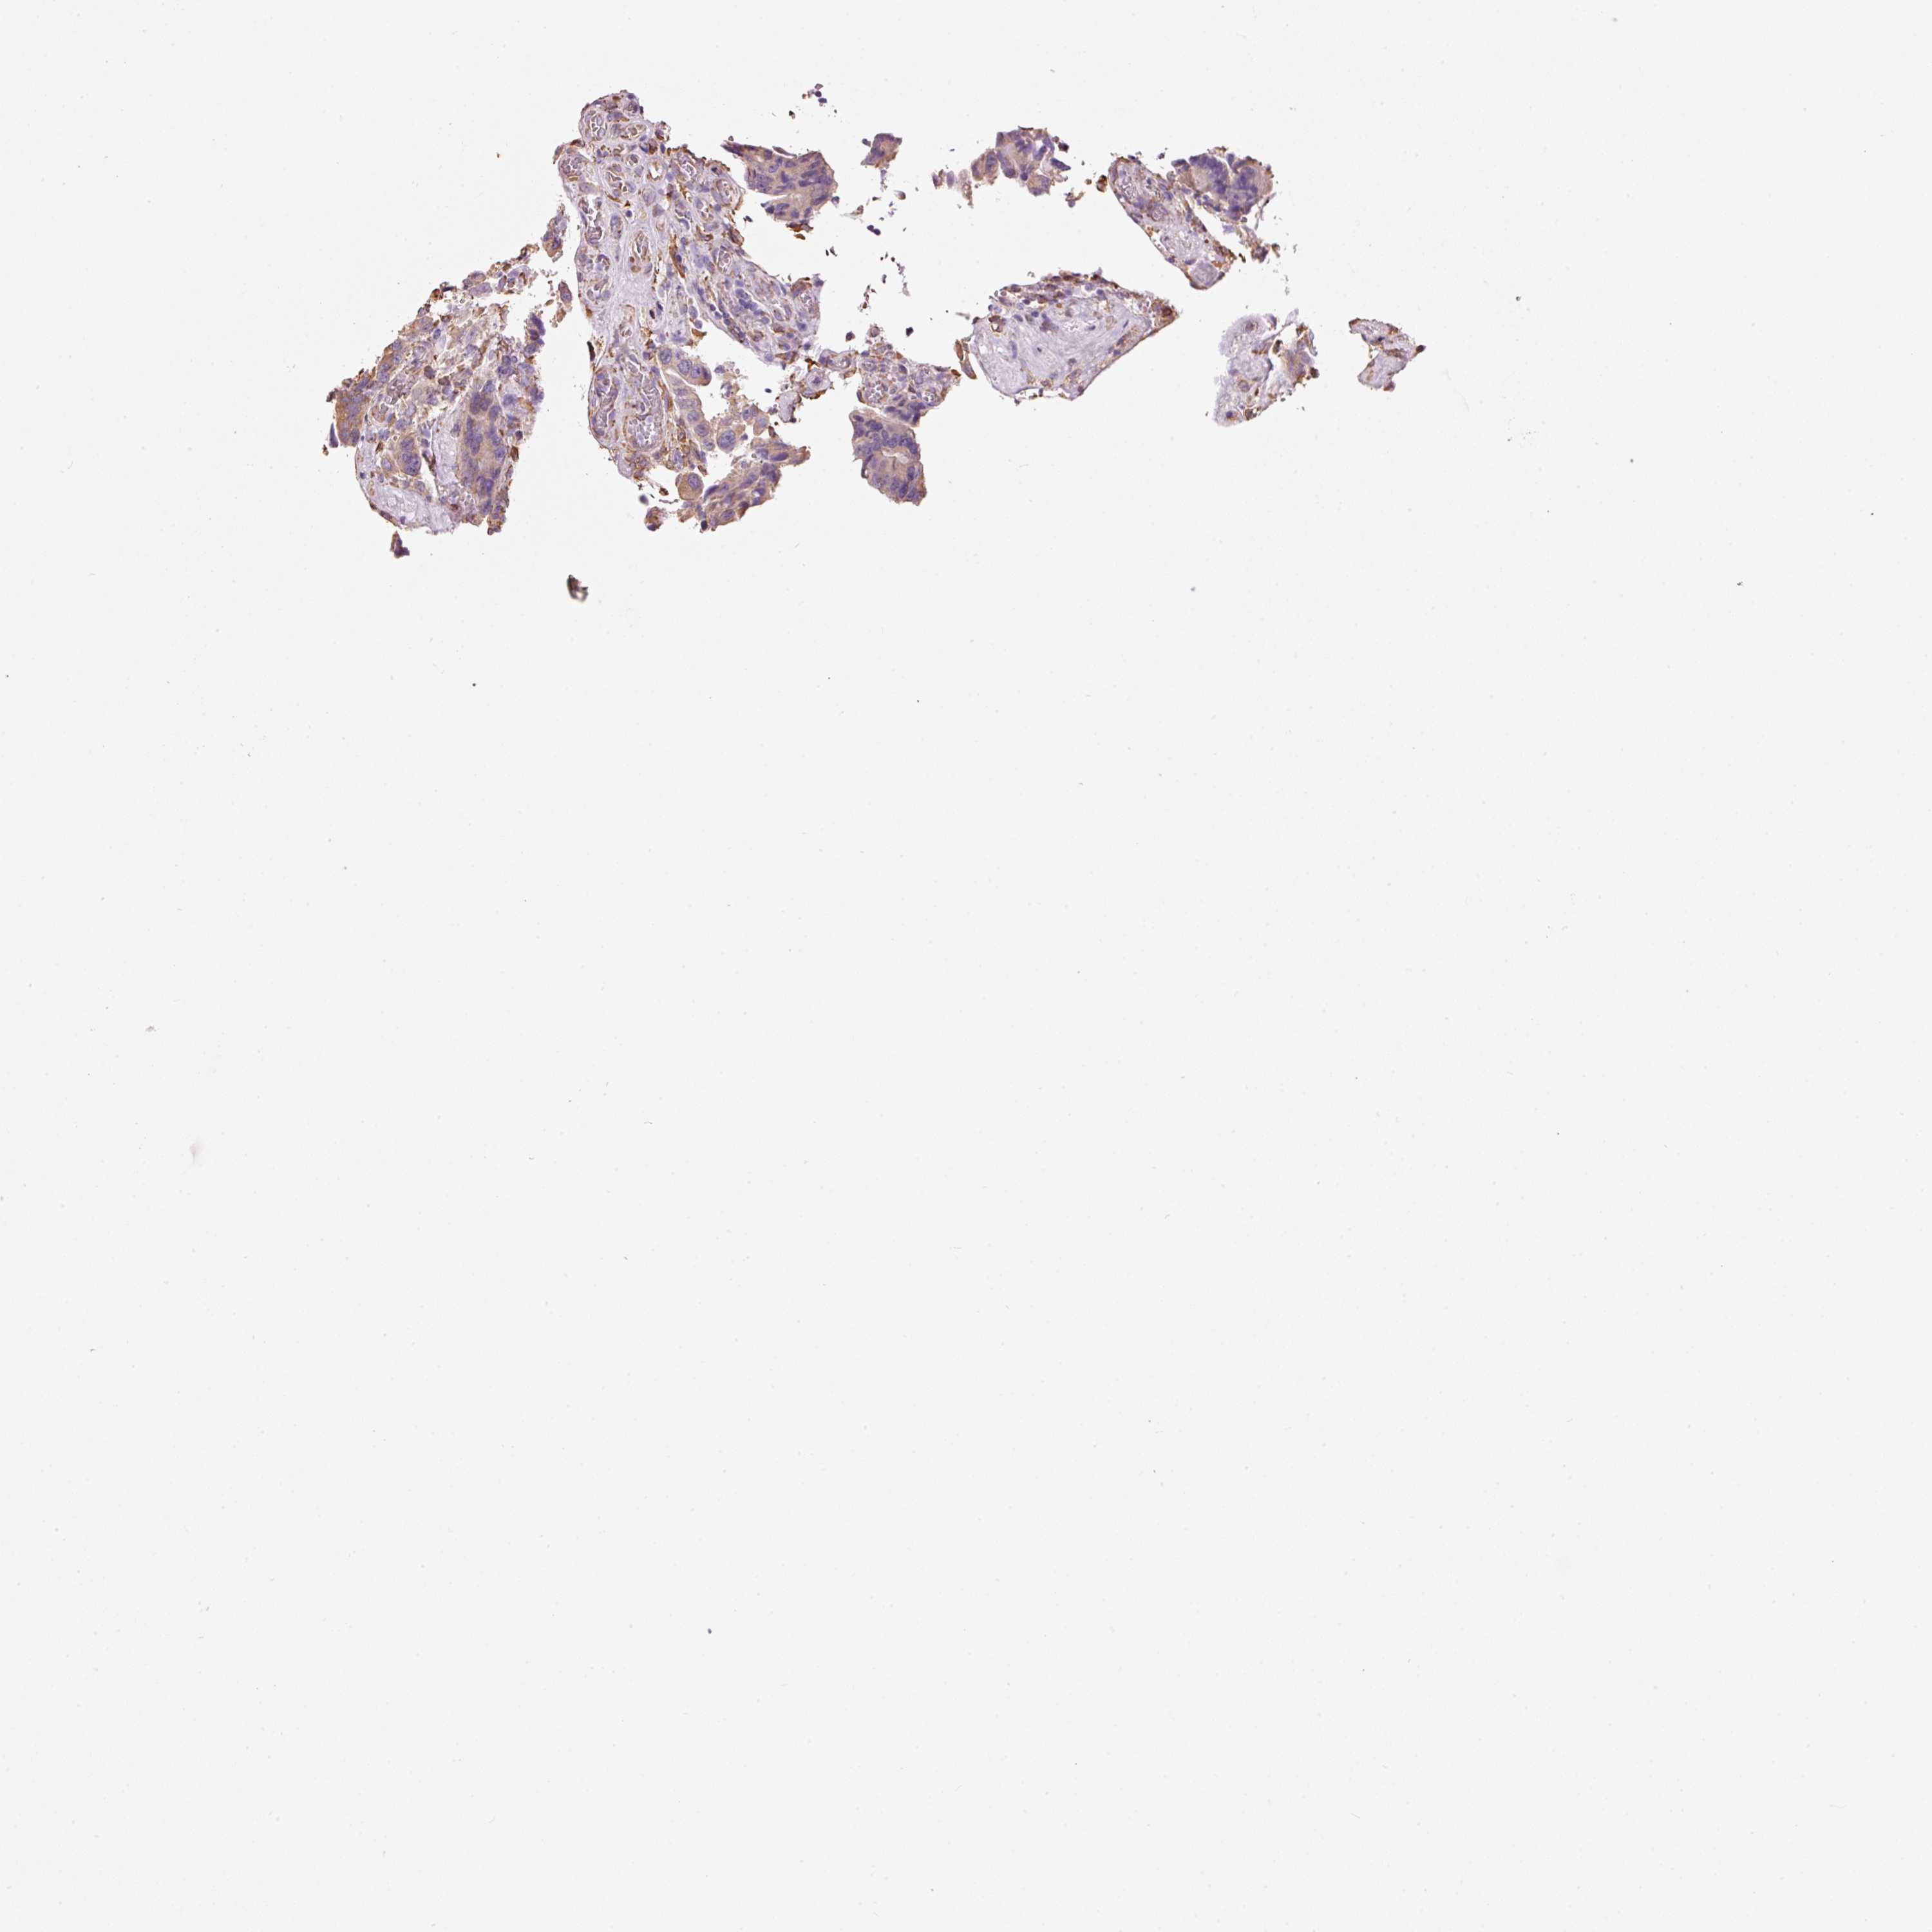

CANCER COLORECTAL CANCER Show tissue menu

Colorectal cancer

Human cancer

Colon adenocarcinoma

Rectum adenocarcinoma